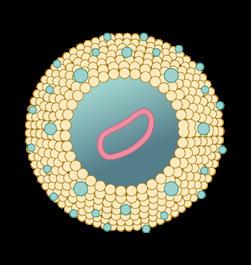

Figura 29. Fármacos que bloquean al sistema renina angiotensina: DRI: inhibidores directos de la renina como aliskirem, ACE-I: inhibidores de la enzima convertidora de angiotensina como captopril o enalapril, ARB: bloqueadores de los receptores de angiotensina II como valsartán o losartán.